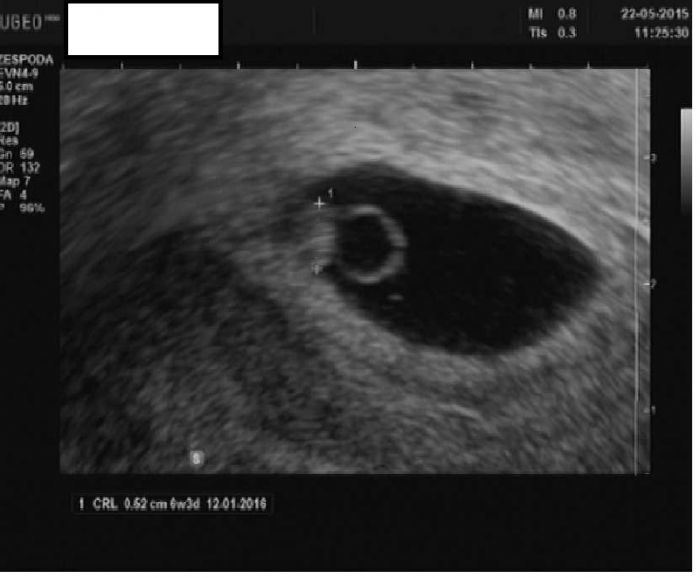

Ahooooj děvčátka! No tak já už mám také první prohlídku za sebou! Měla jsem dnes být 7+2 ale fazolka je trochu menší, měří 0,52mm takže prý tak 6+3, tak snad dobré (termín se tedy posouvá na 12.1)  :) Jsem nadšená - viděla jsem krásně i srdíčko jak bije, bylo to kouzelné! A mám štěstí protože sestřičky i doktorka byly neuvěřitelně milé a prostě paráda! Mám z toho obrovskou radost! Další kontrolu mám až 29.6. což je za děsně dlouho! Tak chvilku vydržte a já vám nahraju i naši první fotečku! A jinak všem gratuluji k novým zjištěním a doufám, že všechny budeme v pořádku :)

Autor: Luci 91   22.5.2015 v 17:22

Tak se jdu chlubit jakou mám parádní fazolku :)))) Dostala jsem k tomu i komentáře od paní doktorky. To velké černé je prý to těhotenství, to kulaté, co vypadá jak prstýnek je ten žloutkový vak nebo co, no a zády je na něj přilepená moje fazolka! Kouká doleva a krásně jí tluče srdíčko! Už bych chtěla mít další fotečky! :) A co vy ostatní? máte také fotečky, se kterými se chcete pochlubit? Projížděla jsem naší konverzaci a našla jsem zatím jen dvě ;-)